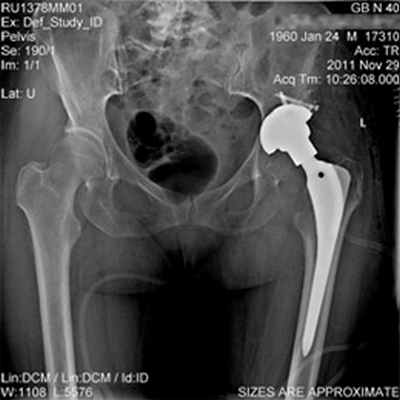

Выполнено тотальное эндопротезирование левого тазобедренного сустава в сочетании с костной аутопластикой.

Пациентка активизирована на 2-е сутки после операции.

На 6-й день после операции пациентка выписана на амбулаторное лечение, после заживления раны, направлена на восстановительное лечение, на контрольных осмотрах отмечается постепенное восстановление функции нижней конечности. В средние сроки (6 недель) пациентке разрешена полная нагрузка на оперированную конечность.

Длина конечности восстановлена, объем движений максимально возможный для тотального эндопротеза тазобедренного сустава, болевой синдром практически купирован. Пациентка может нагружать оперированную конечность всем весом тела.